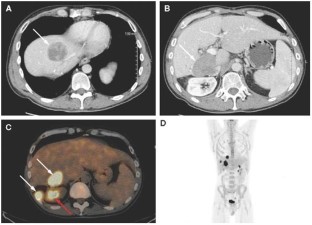

Background A 41-year-old male with a 4-year history of chronic hepatitis C presented with a 1-month history of abdominal pain, fatigue, weight loss, and night sweats.

Investigations Laboratory examinations, chest, abdomen, and pelvic CT scans, PET-CT scans, ultrasound-guided needle biopsies of liver lesions, bone-marrow biopsy, flow cytometry, and immunohistochemical staining for B-cell markers including CD20.

Diagnosis Chemoresistant diffuse large B-cell lymphoma, with gradual loss of CD20 antigen expression.

Management Embolization of hepatic tumors using yttrium-90 microspheres (Therasphere®, Theragenics Corporation, Buford, GA).